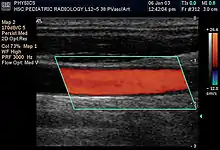

Doppler ultrasonography is medical ultrasonography that employs the Doppler effect to perform imaging of the movement of tissues and body fluids (usually blood),[1] [2] and their relative velocity to the probe. By calculating the frequency shift of a particular sample volume, for example, flow in an artery or a jet of blood flow over a heart valve, its speed and direction can be determined and visualized. Color Doppler or color flow Doppler is the presentation of the velocity by color scale. Color Doppler images are generally combined with grayscale (B-mode) images to display duplex ultrasonography images, allowing for simultaneous visualization of the anatomy of the area.

The Doppler data is displayed graphically using spectral Doppler, or as an image using color Doppler (directional Doppler) or power Doppler (non directional Doppler). This Doppler shift falls in the audible range and is often presented audibly using stereo speakers: this produces a very distinctive, although synthetic, pulsating sound.

There are no standards for displaying color Doppler. Some laboratories show arteries as red and veins as blue, as medical illustrators usually show them, even though some vessels may have portions flowing toward and portions flowing away from the transducer. This results in the illogical appearance of a vessel being partly a vein and partly an artery. Other laboratories use red to indicate flow toward the transducer and blue away from the transducer. Still other laboratories display the Doppler color map in accordance with published data, with red shift representing longer wavelengths (scattered) from blood flowing away from the transducer and blue representing the shorter wavelengths from blood flowing toward the transducer. Because of this confusion and lack of standards, the sonographer must understand the underlying physics of color Doppler and the physiology of normal and abnormal blood flow in the human body (see Red shift).[3][4][5]